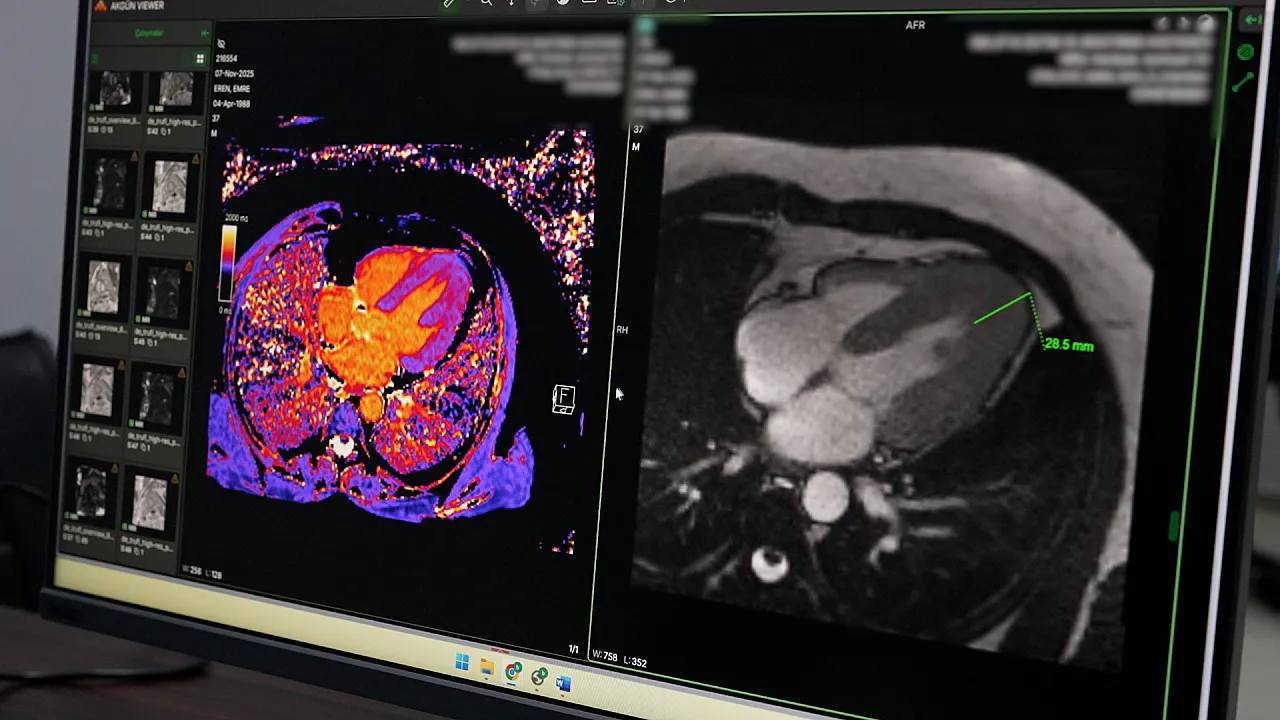

Malatya Turgut Özal Üniversitesi Radyoloji Anabilim Dalı Başkanı Doç. Dr. Bülent Petik, hastanede hayata geçirilen yeniliklere dair çarpıcı bilgiler paylaştı. Bir süredir bölgede Koroner BT Anjiyografi işlemini gerçekleştiren tek resmi kurum olduklarını hatırlatan Petik, bu yöntemin hastalar için büyük kolaylık sağladığını vurguladı. Kalp damarlarının bilgisayarlı tomografi ile saniyeler içinde görüntülenebildiğini belirten Petik, bu sayede klasik anjiyografiye gerek duyulmadan damar darlıklarının ve yapısal bozuklukların net bir şekilde tespit edilebildiğini aktardı.

İleri MR teknolojilerinden biri olan MR spektroskopi ve perfüzyon yöntemlerinin nörolojik vakalarda ve tümör teşhislerinde kritik rol oynadığını ifade eden Doç. Dr. Bülent Petik, somut bir başarı örneğine de dikkat çekti. Kalp yetmezliği şikayetiyle hastaneye başvuran bir kişiye yapılan Kardiyak MR sonucu, tıp literatüründe nadir rastlanan "Yamaguchi Sendromu" tanısı konuldu. Erken ve doğru teşhis sayesinde hastanın hayati riskleri minimize edilerek tedavi süreci başarıyla planlandı.